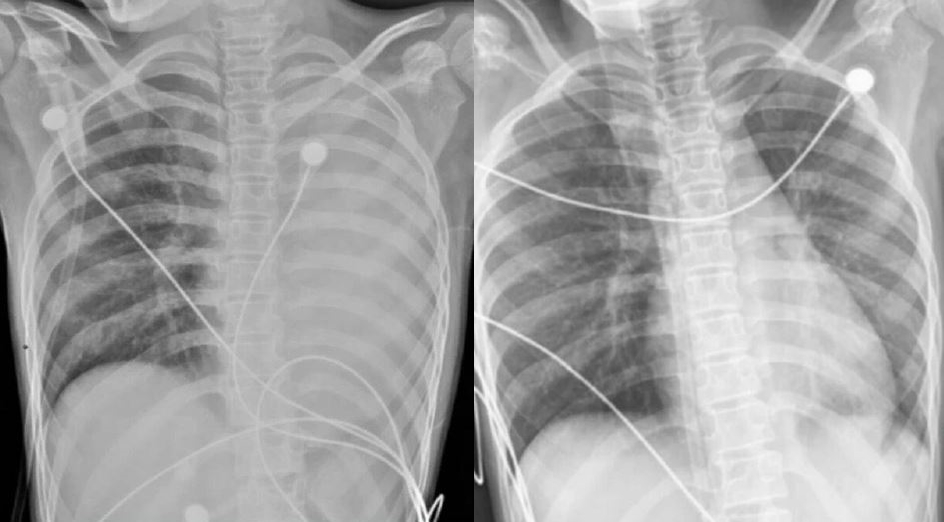

《中國新聞網》報導,這名女孩原本只有輕微咳嗽,之後發燒到38℃,在當地醫院檢查已被診斷為肺炎與肺塌陷。家長察覺病情不對,隨即將她轉送至浙江大學第四醫院。抵達時,女孩已出現呼吸急促與胸悶胸痛,血氧值僅約90%,胸部X光片顯示左肺完全白肺化,情況相當危急。

在緊急安排的支氣管鏡手術中,醫療團隊發現其氣道黏膜明顯紅腫,大量黃白色黏痰持續湧出,左主支氣管與各肺段開口皆被堵死。醫護反覆以負壓吸引、灌洗與鉗取方式清理阻塞物,過程相當艱難,最終才成功打通呼吸道。手術翌日,女孩呼吸困難與胸痛明顯改善,經後續抗感染、化痰與抗發炎治療,最終順利出院。